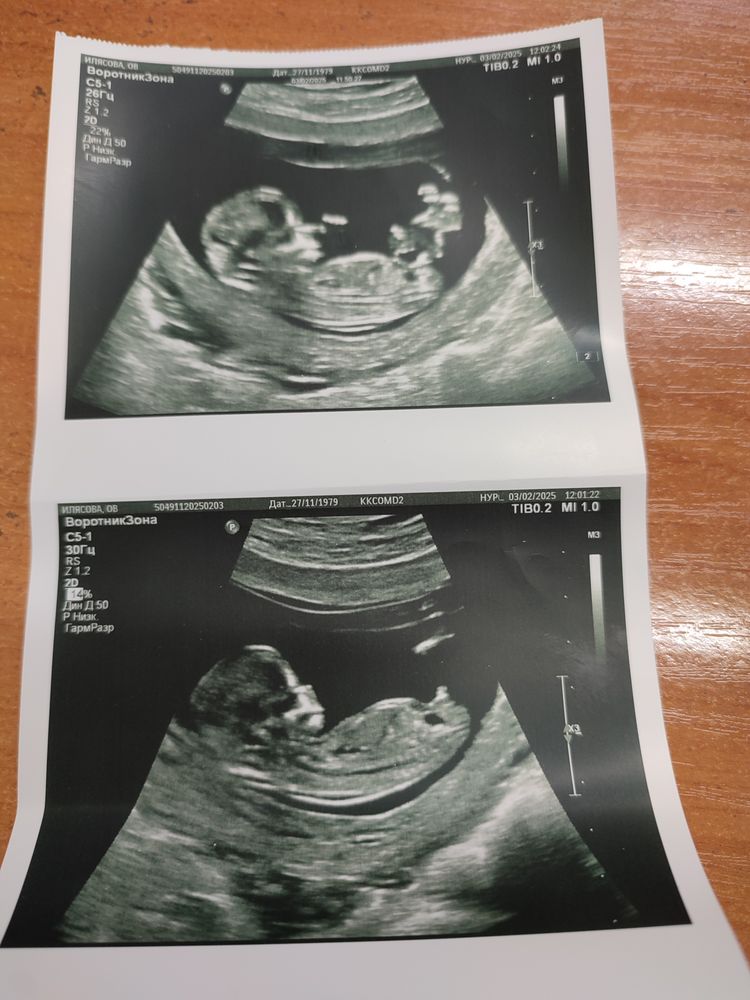

1 скрининг

УЗИОставлю здесь.

У малышастика все хорошо, растёт и развивается как положено, все параметры соответствуют, патологий нет, ждем анализ крови. Для меня масса обследований все возможные УЗИ чего только можно, самое главное обследовать сердце - желудочковая эксосистолия, кто вынашивал с таким диагнозом? Думаю не чего сверх опасного, как всегда нагнетают.

Ну самое главное посмотрела на своего крошку, махал, ручками, ножками, мне до сих пор не верится, что во мне такое чудо!! Слава Богу, что у меня хватило решимости все это принять!!